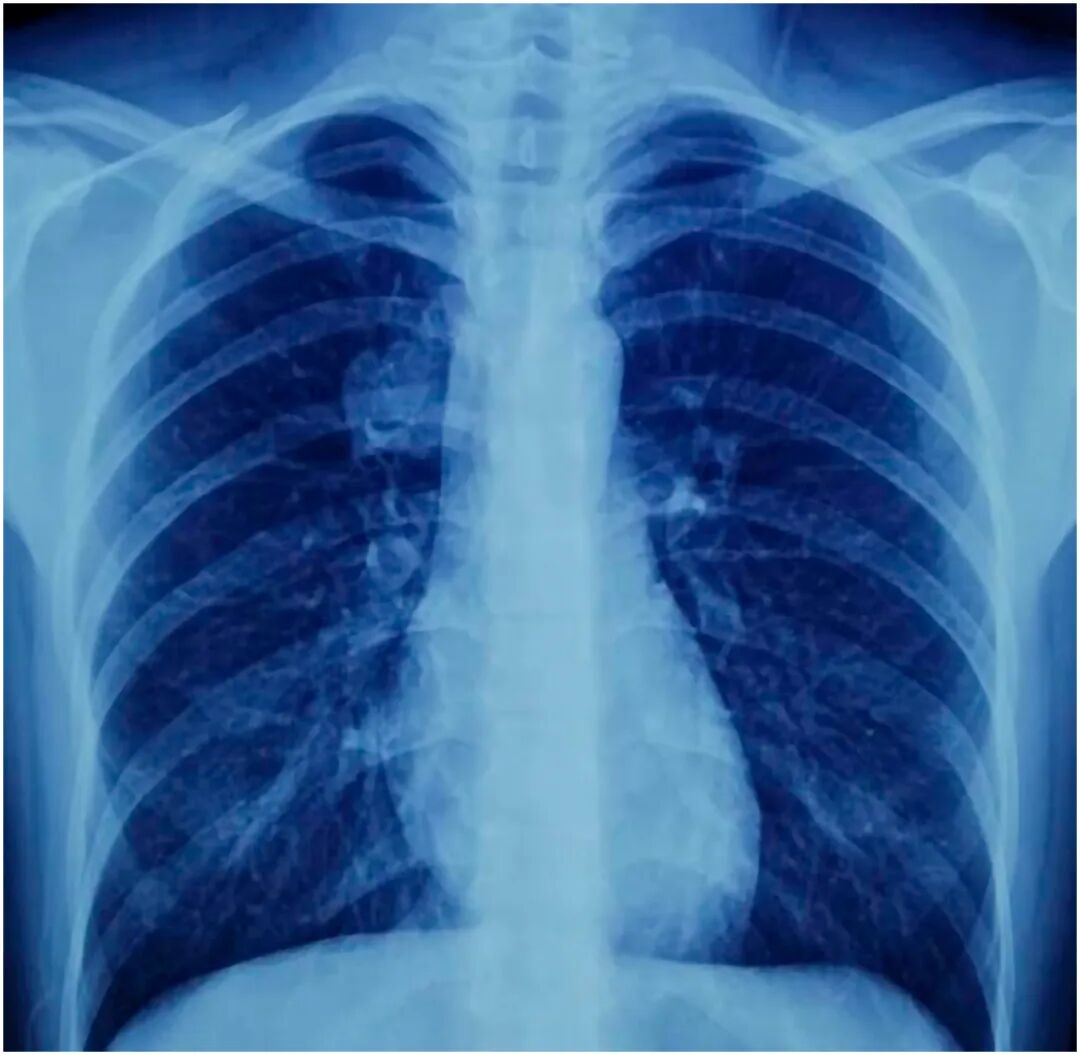

75天后,出现短暂咯血(3天内出现2次),复查纤维支气管镜见气管支气管树充血,手术部位无溃疡、漏气及复发,左肺下叶次级隆突处见小溃疡;胸部X线片示肺完全膨胀,无病灶、血胸、气胸、胸腔积液及肺不张。行支气管肺泡灌洗,细胞学、真菌培养、抗酸杆菌(AFB)及巨细胞病毒基因检测均正常,经治疗后患者恢复良好。